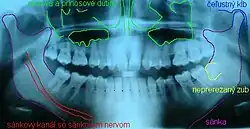

Hypodontie (von altgriechisch ὕπο hypo „unter-“ und ὀδόντος odontos „mit Zähnen“)[1] ist eine Zahnunterzahl. Darunter wird das durch eine Nichtanlage (Agenesie) bedingte Fehlen von einem oder mehreren Zähnen verstanden.[2]

Meistens wird die Nichtanlage von Weisheitszähnen bei der Diagnosestellung nicht berücksichtigt. Nicht angelegte Weisheitszähne werden beim Berechnen der Zahnunterzahl nicht mitgezählt, weil ihr Fehlen relativ häufig ist, keine Zahnlücken bewirkt, kaum Auswirkungen auf Funktion und Aussehen des Gebisses hat und nur schwer zu behandeln wäre.